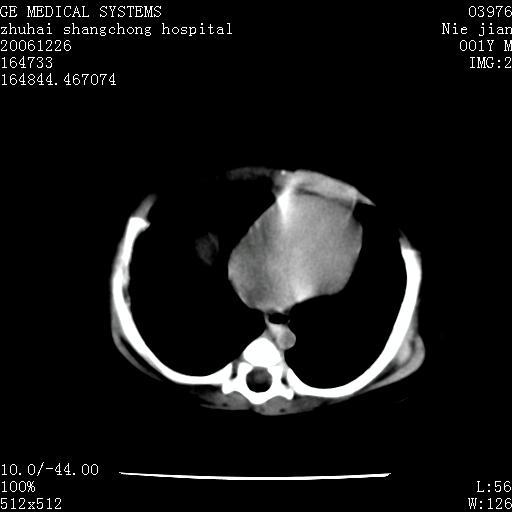

3个月婴儿腹胀来看。

【影像特征】

1、肝明显增大,肝弥漫性低密度灶。

1、关键着眼点:肝脏弥漫性病变内有没有走形的血管,仔细看部分低密度内有血管影(要有增强扫描作为证据就好了),说明并非肿瘤样病变,而是脂肪浸润。即可能不是转移瘤或原发肿瘤,低密度的形态上看,是片状,也不像肿瘤。

2、儿童肝炎最常见的是感染,有时食入性损害或药物也可致肝脏炎症,肝炎致大空泡型脂肪变性,是一种无痛性疾病,无症状,病因有营养异常、代谢性疾病、药物及病毒感染。所以脂肪变性与感染有关。

3、肝炎的结局是肝硬化,而恰恰一年后复查,已有肝硬化表现。肿瘤一般那会消失,那叫奇迹。